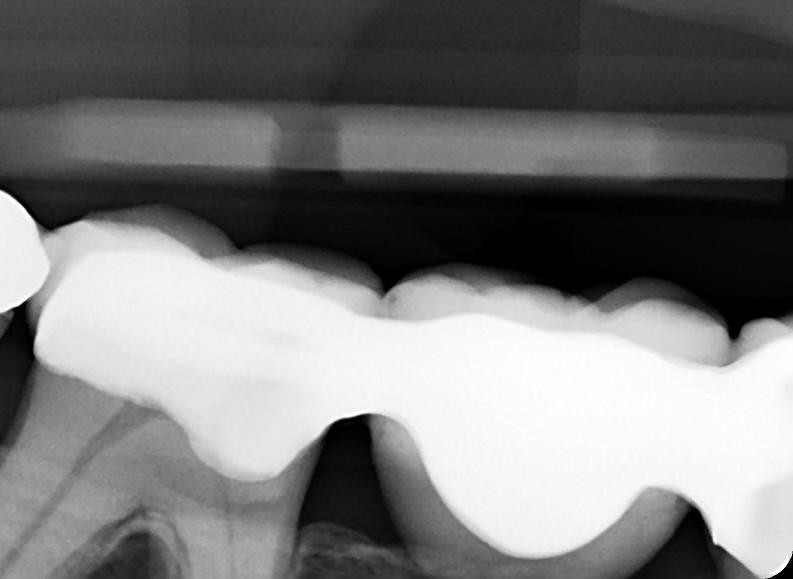

13. What option can be selected for the restoration on the lower jaw?